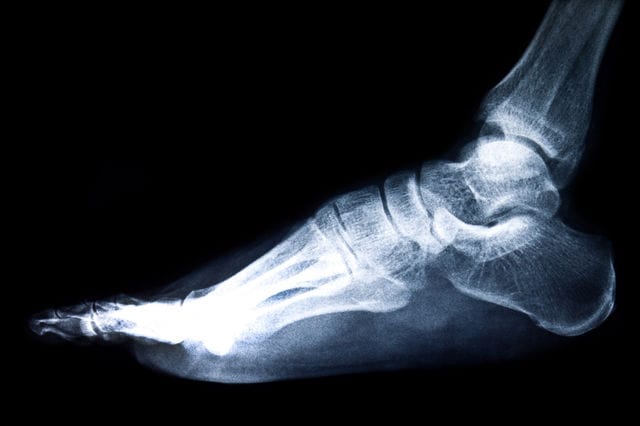

שבר באצבע ברגל הוא סוג של שבר המתרחש באחת מאצבעות הרגל. שברי אצבעות ברגל נפוצים למדי, והם יכולים להיגרם ממגוון סיבות, כגון נפילה, חבלה ישירה או תנועה פתאומית.

שבר באצבע ברגל בוהן שבורה עשויה להיראות כמו פציעה קלה, אך השפעתה על חיי היומיום יכולה להיות משמעותית. למרות גודלה הקטן, בוהן שבורה עלולה לגרום לכאב עצום ולהפריע לתנועתיות. חשוב להבין שגם לשבר קל לכאורה בבוהן יכול להיות השפעה גדולה על הפעילות היומיומית ועל הרווחה הכללית.